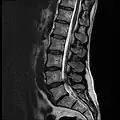

MRI

MRI lumbar spine with degeneration (sagittal T2 FRFSE) -

MRI lumbar spine with degeneration (sagittal T1 FSE) -